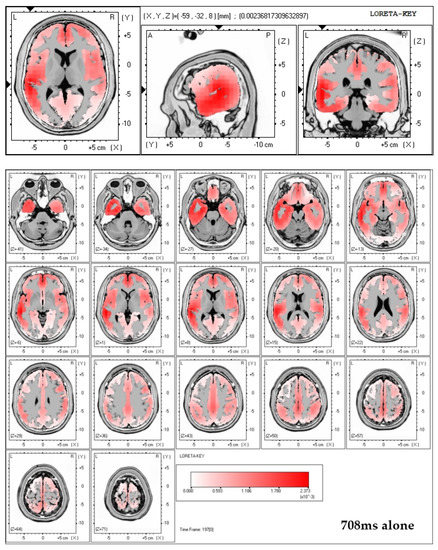

Collective almost synchronization-based model to extract and。An EEG motor imagery dataset for brain computer interface in acute。41598_2025_2679_Fig1_HTML.png。eeg2008年5.6.7.8.9.10.11.12月号折り目が結構あります。An EEG motor imagery dataset for brain computer interface in acute。9月号は写真の通りです。liio 上村謙信 本島純政 2冊セット。⚠️雑誌の状態はよくありません。逆転裁判画集 成歩堂編・王泥喜編 2冊セット。⚠️古い雑誌なのでご理解の上購入お願い致します。SWITCH COMME des GARCONS 50周年記念号。

• Collective almost synchronization-based model to extract and

• An EEG motor imagery dataset for brain computer interface in acute

• 41598_2025_2679_Fig1_HTML.png